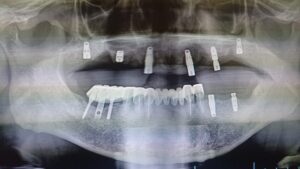

現在、すべて抜けてるインプラントは撤去して、新しく埋入しましたが、新しいものも、しっかり噛めるものを作って差し上げたいと思いました。

(痛みなく除去)

(残せるところは残すのが基本)